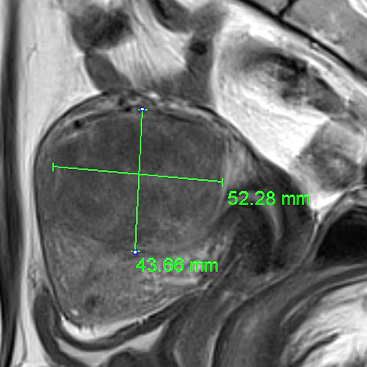

자궁질환치료 특화 시스템 JC200D

작은 초점을 모아 입체적인 종양조직의 괴사를 유도하기 때문에

종양의 크기, 수, 모양, 위치에 따라 개인에 맞는 방법으로 종양조직의 괴사가 가능합니다.

괴사된 체내의 종양은 시간이 지나면 차차 없어집니다.

신형 치료장비